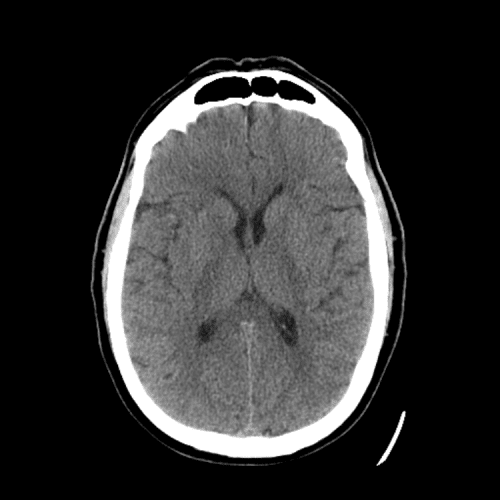

PCA infarct